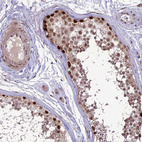

Immunohistochemical staining of human testis shows strong nuclear positivity in cells in seminiferous ducts.